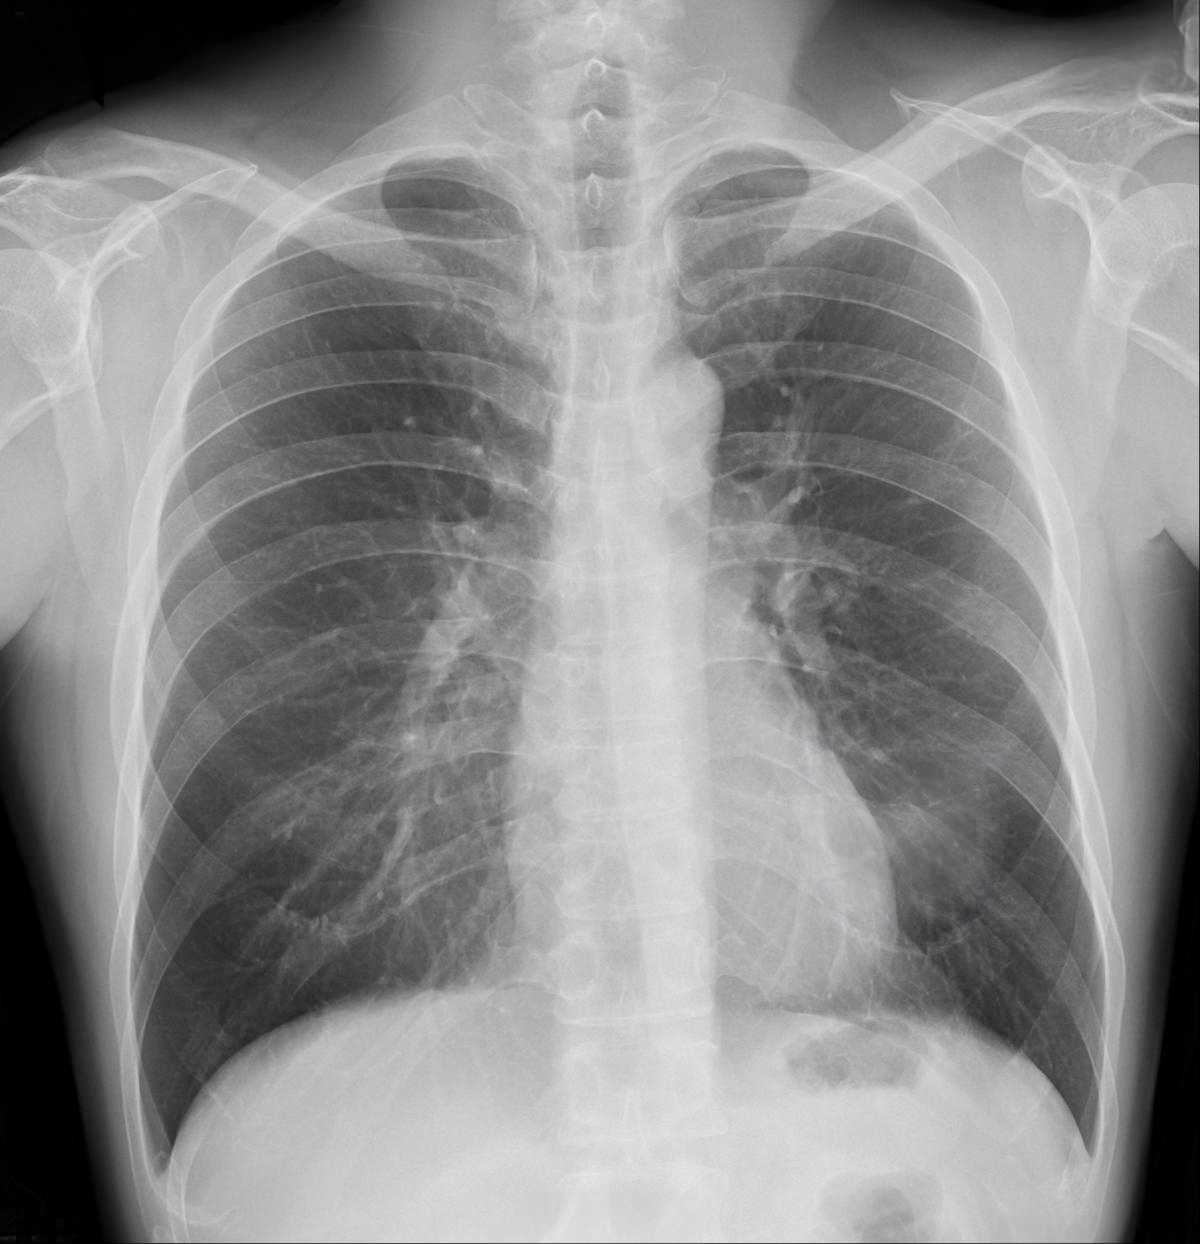

[粉じん作業についての職歴の調査及びエックス線写真による検査]

じん肺用の撮影条件を元に撮影をします。

一般的なレントゲン撮影と同様に息どめ後5秒以内に撮影が完了しますし、放射能も他のレントゲン撮影法に比べて低くなりますので、侵襲性は低いです。

この写真撮影で初見が見られた場合には、各医療機関にて肺機能検査などの追加検査を受けていただきます。